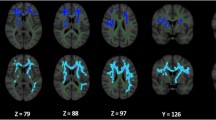

Pronounced patterns of FA differences emerged when stratifying PD participants according to HY stage. HY1 participants (n = 275) had higher FA across the entire WM skeleton (d = 0.30) as well as 4 out of 21 regions of interest (ROI) compared to controls (n = 885), with effect sizes ranging from d = 0.18 to 0.19 (all p < 0.05, false discovery rate corrected24). Implicated regions included the anterior corona radiata, anterior and retrolenticular parts of the internal capsule, and the genu of the corpus callosum. Higher FA in HY1 participants was in the 1.0–1.4% range across significant ROIs. HY2 PD participants (n = 742) had lower FA at the fornix (d = −0.26) relative to controls, a reduction in FA of 5.4%. HY3 PD participants (n = 220) had lower FA across the entire WM skeleton (d = −0.24), as well as 9 out of 21 ROIs, with the largest effect at the fornix (d = −0.33). Implicated regions include the anterior and posterior corona radiata, posterior thalamic radiation, genu of the corpus callosum, external capsule, fornix/stria terminalis, superior longitudinal fasciculus and the sagittal stratum. Lower FA in HY3 participants was in the 1.3–7.3% range across significant ROIs. HY4/5 PD participants (n = 75) had lower FA across the entire WM skeleton (d = −0.74), as well as 20 out of 21 ROIs relative to controls, with the largest effect in the fornix (d = −1.01) and remaining values increasing in magnitude from d = −0.26, representing between 1.4% and 18.9% lower FA. The only ROI not implicated in HY4/5 participants was the cingulum (hippocampal portion) (Fig. 1A; Supplementary Results 1.4.1).

HY1 PD participants displayed higher FA across the entire WM skeleton (d = 0.27) as well as 3 out of 21 ROIs, relative to matched controls (n = 275), with effect sizes ranging from d = 0.23 to 0.24. Implicated regions included the anterior corona radiata and the anterior and posterior limb of the internal capsule, representing between 0.9% and 1.5% higher FA. HY2 PD participants demonstrated significantly lower FA in the fornix (d = −0.27), relative to matched controls (n = 742), a reduction in FA of 5.6%. HY3 PD participants displayed lower FA in the fornix (d = −0.31) and the sagittal stratum (d = −0.29), relative to matched controls (n = 220), a reduction in FA of 2.1% and 6.7%, respectively. HY4/5 PD participants displayed widespread significant differences in FA across the entire WM skeleton (d = −0.56) as well as 18 out of 21 ROIs, relative to matched controls (n = 75), with effect sizes ranging from d = −0.38 to −1.09. Lower FA in HY4/5 participants was in the 3.0% to 19.0% range across significant ROIs. ROIs not implicated include the retrolenticular and posterior limb of the internal capsule and the corticospinal tract (Fig. 1B; Supplementary Results 1.4.2).

HY1 PD participants displayed lower MD across the entire WM skeleton (d = −0.19) as well as 5 out of 21 ROIs, relative to controls, with effect sizes ranging from d = −0.18 to d = −0.27. Implicated regions include the anterior and retrolenticular limbs of the internal capsule, the fornix/stria terminalis, cingulum (hippocampal portion) and the sagittal stratum. Lower MD in HY1 participants was in the 1.3–2.1% range across significant ROIs. HY2 PD participants displayed lower MD at the fornix/stria terminalis (d = −0.22), as well as 2 out of 21 ROIs relative to controls, with effect sizes of −0.19 and −0.18 at the retrolenticular limb of the internal capsule and the cingulum (hippocampal portion), respectively. Lower MD in HY2 participants was in the 1.2% to 1.9% range across the significant ROIs. HY2 participants also displayed higher MD at the fornix (d = 0.15), an increase in MD of 3.2%. There were no significant MD differences in HY3 PD participants relative to controls. HY4/5 PD participants displayed higher MD in the fornix (d = 0.69) as well as 6 out of 21 ROIs, relative to controls, with effect sizes ranging from d = 0.33 to 0.46. Implicated regions include the anterior and superior corona radiata, external capsule, genu and body of the corpus callosum and the superior fronto-occipital fasciculus. Higher MD in HY4/5 participants was in the 1.9% to 13.1% range across the significant ROIs. HY4/5 PD participants also displayed lower MD in the cingulum (hippocampal portion) (d = −0.32) relative to controls, a reduction in MD of 3.2% (Fig. 2A; Supplementary Results 1.4.3).

There were no significant differences in MD in HY1 PD participants relative to matched controls. HY2 PD participants demonstrated significantly lower MD at the fornix/stria terminalis (d = −0.22), as well as 3 out of 21 ROIs, relative to matched controls (n = 742), with effect sizes ranging from d = −0.14 to −0.19. Implicated regions include the posterior limb and the retrolenticular parts of the internal capsule as well as the cingulum (hippocampal portion). Lower MD in HY2 participants was in the 0.8% to 2.0% range across the significant ROIs. These participants also showed higher MD at the fornix (d = 0.15), an increase in MD of 3.3%. There were no significant MD differences in HY3 PD participants relative to matched controls, while HY4/5 PD participants displayed significantly higher MD at the fornix (d = 0.72) relative to matched controls, an increase in MD of 13.0% (Fig. 2B; Supplementary Results 1.4.4).

We found significantly higher FA in HY1 participants across the entire WM skeleton, lower FA of the fornix in HY2 participants, and lower FA across the vast majority of the WM skeleton in participants at HY stages 3 and 4/5. While the study is cross-sectional, we can see evidence of a progression of effect sizes, where results from early disease stages present as very small effects, while those at advanced disease stages showing medium and large effect sizes. In the HY1 PD participants, the largest effect sizes were found for the higher FA in the internal capsule and anterior corona radiata. These structures are key components of the cerebello-thalamo-cortical and basal ganglia-cortical loops and likely play an important role in the pathophysiology of tremor in PD. It has been suggested that tremor signals originating in the basal ganglia ascend via the ventrolateral nucleus of the thalamus through the internal capsule to the corona radiata where they radiate out to the cortex26. One study found that increased FA is associated with tremor-dominant PD, relative to postural instability-gait disturbance PD, impacting multiple brain regions including the corpus callosum, forceps minor, bilateral thalamic radiation, bilateral superior and inferior longitudinal fasciculi and the left sagittal stratum, suggesting an important relationship between this motor phenotype and DTI abnormalities in PD27. The fornix also shows among the largest effect sizes in PD; FA was significantly reduced here in HY2, HY3 and HY4/5 participants. The fornix is a major hippocampal output structure that traverses longitudinally from the mesial temporal lobes to the diencephalon and basal forebrain, and it plays a key role in cognition and episodic memory recall28. Here we show that this structure is greatly impacted in PD, with a significant correlation between FA and cognitive performance.

We identified significantly lower MD across the entire WM skeleton at the HY1 stage, while in HY2, this result was confined to the internal capsule, fornix/stria terminalis and the cingulum (hippocampal portion). In HY3, there were no significant differences in MD, while HY4/5 participants showed significantly higher MD at widespread regions of interest. Some of the significant MD findings were not observed when comparing PD cohorts to age- and sex-matched controls, with only the most robust effect sizes remaining significant. In our correlational analyses, the effect sizes generated at the matched and unmatched levels of analysis had the same direction and were highly correlated, suggesting that the lack of significant results when comparing MD in HY3 and HY4/5 groups with age- and sex-matched controls are likely due to differences in sample size and statistical power, as well as removing confounding effects. Similar to our results for the FA analyses, in HY1 and HY2 participants large effect sizes were found for regions of interest in the internal capsule, further highlighting this region as an important neuroanatomical structure in PD. In HY4/5 participants, we also found significantly higher MD in the fornix, and MD of the fornix was inversely correlated with performance on the MoCA test.